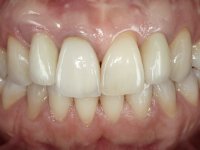

Paciente do sexo feminino, com 36 anos de idade, não fumadora. Apresentava o dente 1.1 com uma tonalidade mais escura que os dentes adjacentes. Feito o exame imagiológico, observou-se que o dente 1.1 tinha tratamento endodôntico, a paciente tinha 3 implantes colocados, dois no local dos dentes 1.2 e 2.2 e o outro no 4.6. A paciente tinha sido tratada ortodonticamente, apresentava um fenótipo gengival médio e uma boa higiene oral. Após 5 anos da primeira intervenção a paciente apresenta-se na consulta com sintomatologia infeciosa compatível com uma peri-implantite nos implantes 1.2 e 4.6. Após exame clínico, foi confirmada imagiológicamente. A perda óssea vertical tinha mais de 4mm nas duas situações.

Na primeira intervenção foi proposto à paciente uma coroa total com infraestrutura em Zr revestida por cerâmica. O facto do dente ter um tratamento endodôntico foi determinante nesta opção. Na segunda intervenção, foi proposto a remoção dos dois implantes. No implante colocado no local do dente1.2 seria feita uma regeneração óssea simultânea à colocação do novo implante. Contando com a inevitável retração gengival na zona cervical da coroa do 1.1, foi também proposto refazer a coroa do dente 1.1. Foi também adiantado que por questões de simetria, se fosse necessário, também poderia ter que se intervir no dente 2.2. Assim, na zona antero-superior, teríamos coroa aparafusada sobre um novo implante colocado no 1.2, nova coroa no1.1 e uma faceta ou coroa no dente 2.1 se necessário. No implante colocado na zona do 4.6, propomos removê-lo, colocar um novo implante, posteriormente reabilitado com uma coroa aparafusada.

Após 5 anos da primeira intervenção, a paciente surge na consulta com uma peri-implantite nos implantes colocados no local dos dentes 1.2 e 4.6. Começamos por abordar a peri-implantite no local do dente 2.2. Foi feita uma ponte provisória de laboratório em acrílico com 2 elementos. O dente 1.1 como pilar e o 1.2 como pôntico, este último apresentava um apoio distal. A coroa do 1.2 foi removida do coto com um corte longitudinal feito com turbina e depois foi fraturada com um mini luxador. O coto foi de seguida desaparafusado do implante. Fez-se o mesmo procedimento para remover a coroa do 1.1. O dente 1.1 foi re-preparado e a ponte provisória foi rebaseada em boca com acrílico autopolimerizável. Feito o correto acabamento e polimento da provisória foi feita a sua cimentação temporária com cimento de policarboxylato. Numa consulta posterior. foi feita a remoção da ponte provisória, feita a cirurgia para explantação do implante, colocou-se um novo implante e fez-se a regeneração óssea da zona com uma membrana não reabsorvível. 3 meses após foi removida a coroa do implante colocado no 4.6. Foi feito um corte horizontal com turbina na zona cervical e com um mini luxador descolou-se a coroa do coto. Após este procedimento fez-se a explantação do implante. Após 6 meses foi colocado um novo implante no local do 4.6. Após a osteointegração foi feita a impressão com a técnica de moldeira aberta e foi confecionada em laboratório uma coroa aparafusada sobre o implante. Aprovada pela paciente foi apertada definitivamente em boca. Após 1 mês removemos a ponte provisória antero-superior, reforçamos o dente 1.1 com um poste intra- radicular e reconstruimos o coto com uma resina de polimerização dual. Nessa mesma consulta expomos o implante colocado no 1.2 e fizemos uma impressão pela técnica de moldeira aberta com silicone de dupla viscosidade e presa rápida. No laboratório foi feita uma ponte provisória de 2 elementos, aparafusada sobre o implante e cimentada sobre o dente. A primeira ponte provisória foi removida e colocada a segunda aparafusada sobre o implante. A linha de acabamento cervical do 1.1 foi rebaseada com resina composta durante o aperto do parafuso do implante. Depois foi removida, foram feitos os acabamentos e finalmente apertada sobre o implante e cimentada temporariamente sobre o dente. Após 2 meses de maturação dos tecidos moles em função do perfil de emergência criado pela nova ponte provisória, pudemos avaliar a estética conseguida em conjunto com a paciente. Neste longo processo o dente 2.1 teve que fazer um tratamento endodôntico. Decidiu-se assim fazer também uma coroa no dente 2.1.O dente 2.1 foi preparado na mesma consulta em que se fez a impressão ao implante. A ponte provisória foi utilizada para individualizar a peça de transferência, copiando o seu perfil de emergência e em seguida foi realizado o afastamento gengival com caolino. A impressão foi feita com a técnica de moldeira aberta com silicone de dupla viscosidade e presa rápida. Após a escolha da cor, a impressão foi enviada  para o laboratório onde foram confecionadas 2 coroas  com infraestrutura em Zr. revestidas a cerâmica para os dentes 1.1 e 2.1 e uma coroa aparafusada sobre o implante no dente 1.2. O trabalho final foi aprovado pela paciente e foi colocado definitivamente em boca. A coroa sobre o implante foi aparafusada com 35 N e as coroas foram cimentadas com cimento de ionómero de vidro reforçado com resina.